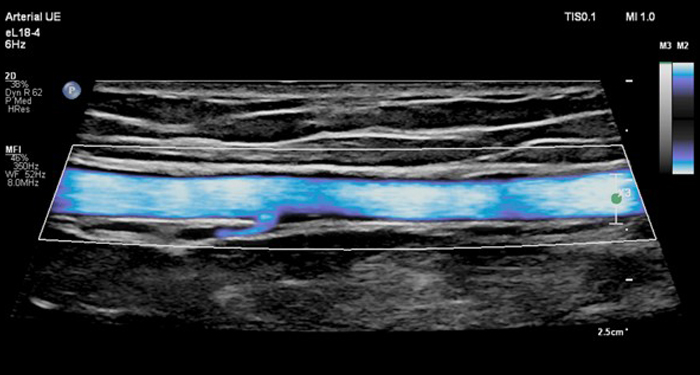

La sonde eL18-4 avec MicroFlow Imaging est une sonde spécialisée pour les services d’exploration vasculaire qui souhaitent repousser les limites de leurs services d’échographie. La sonde eL18-4 offre un nouveau niveau de performance dans les domaines suivants : La nouvelle sonde eL18-4 avec MicroFlow Imaging est la première sonde PureWave linéaire haute fréquence qui permet au clinicien d’obtenir à la fois une résolution en champ proche et une pénétration supérieures

Le nouveau mode d’imagerie Philips MicroFlow Imagingpermetde détecter les flux de très faible vitesse et de petit calibre au sein des tissus. Il fournit des détails remarquables et un niveau de sensibilité élevé.